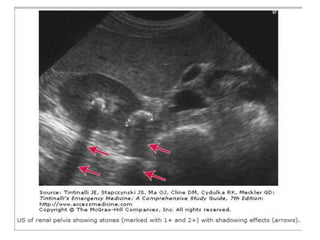

ULTRASON

• BT için uygun olmayan hastalar usg ile

değerlendirilebilir.

• Tanıya yardımcıdır.

• Hidronefroz için %98 sensitiftir

• Usg de hidronefroz denilenlerin %22 si normal

variasyon , kist yada dolu mesaneye bağlıdır.

• Hızlı kristalloid infizyonu yanlış pozitif

hidroureter gösterebilir.

• Doppler görüntülemesiyle renal kan akımı

hakkında fikir verir.

• Ucuz , güvenli ve yan etkisiz bir yöntemdir.

• Obezlerde görüntüleme güçtür.

• Operatöre çok bağlıdır.

• Acil tıp hekimlerinin renal usg başarısı

yüksektir.

ULTRASON • BT içinuygun olmayan hastalar usg ile değerlendirilebilir. • Tanıya yardımcıdır. • Hidronefroz için %98 sensitiftir • Usg de hidronefroz denilenlerin %22 si normal variasyon , kist yada dolu mesaneye bağlıdır. • Hızlı kristalloid infizyonu yanlış pozitif hidroureter gösterebilir.

• Doppler görüntülemesiylerenal kan akımı hakkında fikir verir. • Ucuz , güvenli ve yan etkisiz bir yöntemdir. • Obezlerde görüntüleme güçtür. • Operatöre çok bağlıdır. • Acil tıp hekimlerinin renal usg başarısı yüksektir.